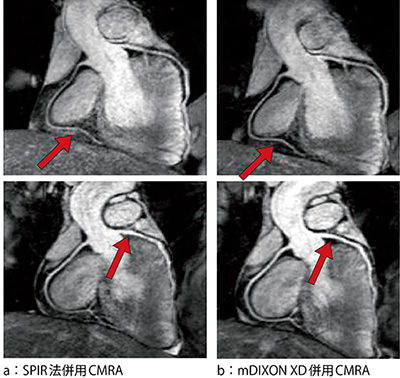

現在,mDIXON XDに期待されている領域は心臓領域,特に冠動脈撮像である。MRIによる冠動脈撮像は,balanced SSFPシーケンスにSPIR法などの脂肪抑制を併用したwhole heart coronary MRA(以下,CMRA)が広く臨床応用されている。mDIXON XDがCMRAにもたらす特長としては,高い脂肪水分離による画質向上が挙げられる。図1は,SPIR法を併用したCMRAとmDIXON XDを併用したCMRAのwater imageである。SPIR法を併用したCMRAは,心臓周囲脂肪のわずかな抑制不良が冠動脈の背景信号として存在しているが,mDIXON XDを併用したCMRAは精度の高い脂肪水分離により心臓周囲脂肪が抑制されていることが確認できる。SPIR法では単一脂肪の周波数のみに脂肪抑制パルスを照射するが,それ以外の周波数を示す複数の脂肪には対応していないため脂肪抑制不良を示している。一方,mDIXON XDは前述のとおり,脂肪のマルチピークモデルを採用していることからわずかな脂肪信号も排除し,冠動脈と周囲脂肪のコントラスト比が向上し,画質改善をもたらすことが可能である2),3)。また,mDIXON XDは,冠動脈を高信号に示すwater imageのほかに脂肪信号のみを反映したfat imageも再構成されるため,fat imageを用いた冠動脈外観の評価も可能である(図2)。例えば,water imageにより冠動脈狭窄が疑われた場合,fat imageによる血管外観を併せて観察することによりアーチファクトなどによる偽狭窄の判別が可能となり,さらなる診断能向上が期待されている。

図1 CMRAにおけるSPIR法とmDIXON XDの比較